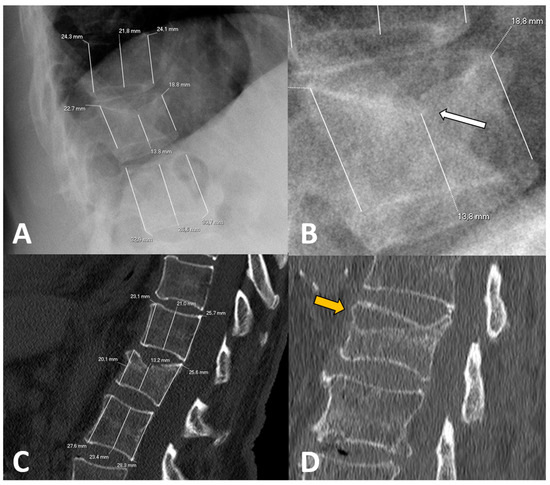

| Loss of anterior height (X-rays) | 26.1 ± 15.8 | 29.3 ± 17.8 | 22.9 ± 12.9 | 0.054 |

| Loss of middle height (X-rays) | 29.9 ± 12.3 | 32.4 ± 13.2 | 27.4 ± 11.0 | 0.052 |

| Loss of posterior height (X-rays) | 9.5 ± 10.3 | 12.3 ± 11.1 | 6.7 ± 8.7 | 0.009 * |

| Loss of anterior height (CT) | 19.5 ± 14.1 | 23.5 ± 14.9 | 15.6 ± 12.1 | 0.007 * |

| Loss of middle height (CT) | 25.5 ± 14.1 | 28.1 ± 15.5 | 22.8 ± 12.2 | 0.074 |

| Loss of posterior height (CT) | 7.8 ± 8.5 | 9.7 ± 10.0 | 5.9 ± 6.1 | 0.032 * |